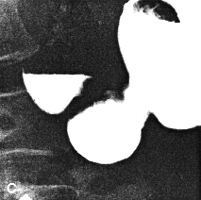

Case 37.3. F.J., 64 year old female with longstanding, non-insulin dependent diabetes mellitus had received oral anti-diabetic therapy for 8 years. She was admitted for dyspepsia, epigastric pain and diabetic retinopathy. Upper gastrointestinal radiological examination showed a small benign-looking gastric polyp immediately below the gastro- oesophageal junction. Gastric peristaltic waves were shallow and appeared sluggish. The pyloric sphincteric cylinder was partially contracted throughout the examination; while minor degress of movement of the walls were discernable, there was a total lack of cyclical contraction and relaxation, the appearance remaining more or less unchanged (Fig. 37.3). The pyloric aperture remained patent, having a diameter of approximately 1.0 cm; continuous emptying of fluid barium occurred through the patulous pylorus. At gastroscopy a small, benign polyp was removed. The remainder of the stomach, the pylorus and duodenum showed no lesion. The motility disturbance of the pyloric sphincteric cylinder with the patulous pyloric aperture was thought to be compatible with diabetic gastroparesis.

![]() | |

| Fig. 37.3. A-D Case F.J. Pyloric sphincteric cylinder permanently contracted. Cyclical activity absent. Pyloric aperture patulous with diameter of 1.0 cm | |